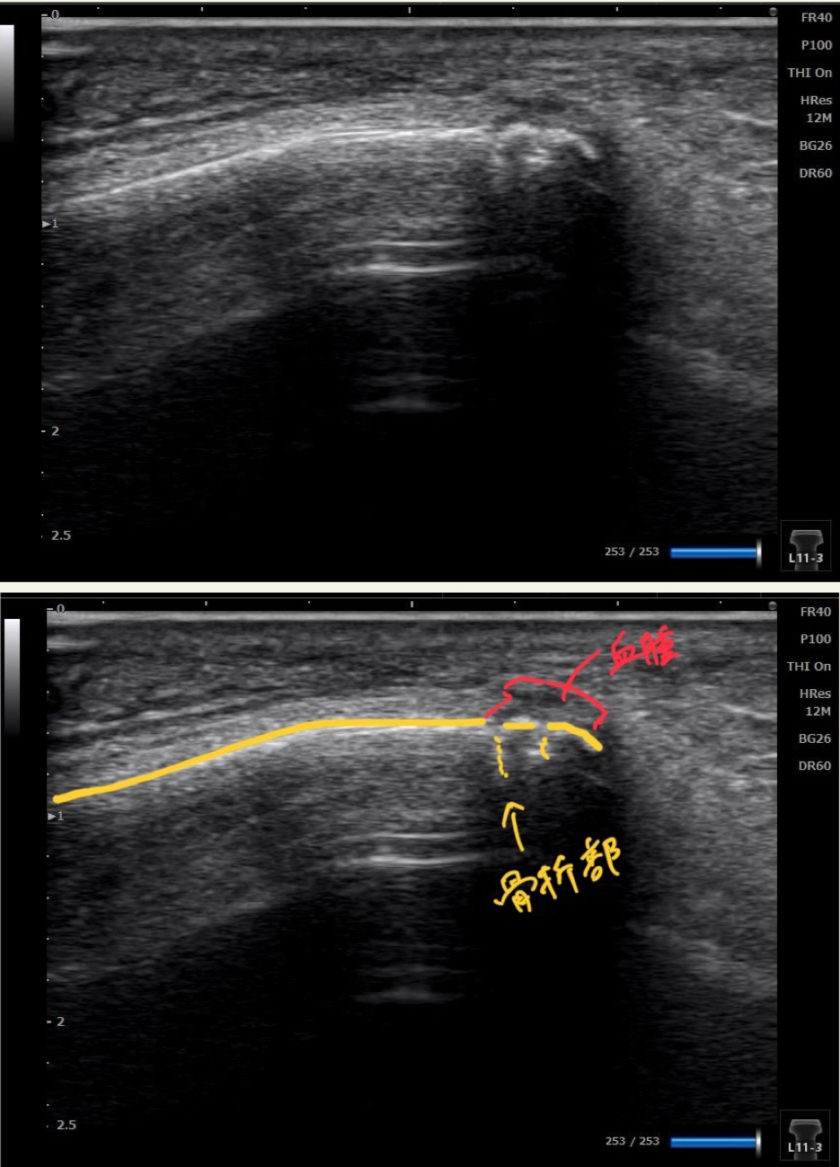

観察すると、外果(外くるぶし)の下方に皮下出血があり、腓骨遠位端を押すとピンポイントで強い痛みを訴えました。これは骨折を強く疑う所見です。

そこでエコーを用いて確認すると――やはり骨折を疑う画像がしっかり観察できました。